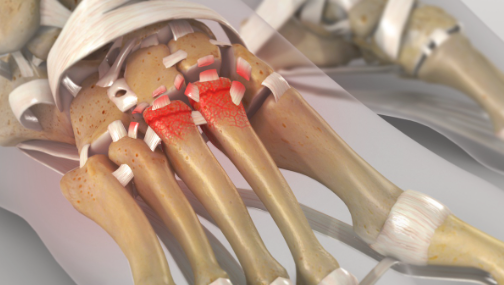

Joints are covered by articular cartilage which allows a bone to glide over another without symptoms. In the case of arthritis this covering is lost with the bones grinding and subsequent pain.

Investigations will enable us to confirm which joint or joints are arthritic. There are no joint replacements available for this area of the body. Given that the movement in this part of the foot is minimal, most patients fair well with fusion of the affected joints.

The prognosis following the surgery should be resolution of this arthritis pain. However, the more joints that are fused the stiffer the foot becomes with an increasing requirements on the surrounding joints to compensate, over time this can result in these joints showing wear and tear.